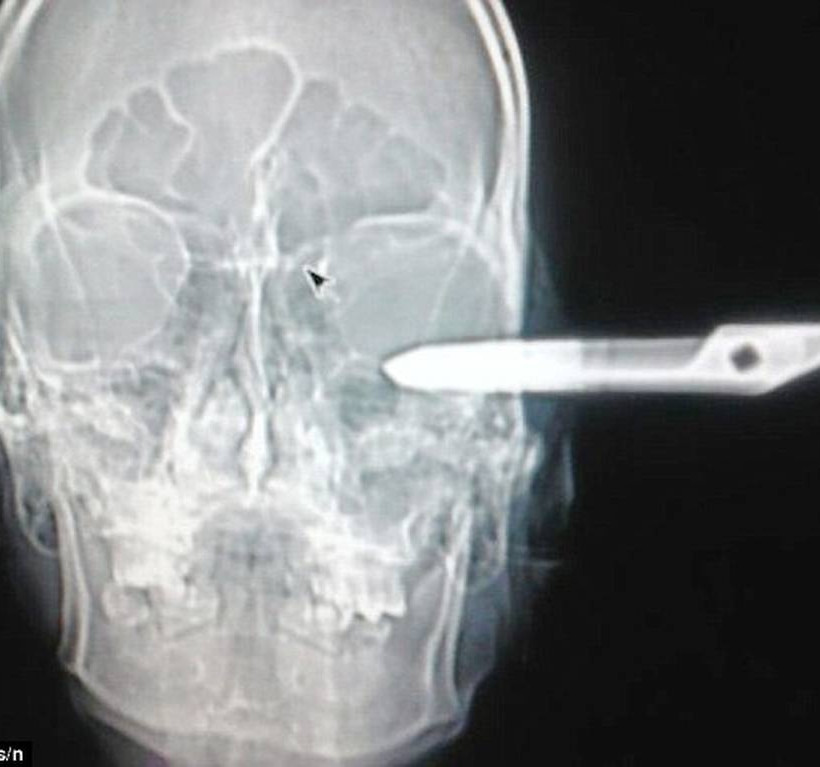

Ο 32χρονος Jonas Acevedo Monroy, χωρίς να φταίει όπως είπαν αργότερα οι αυτόπτες μάρτυρες, έγινε θύμα ενός επιθετικού ντόπιου σε ένα μπαρ, ο οποίος του κάρφωσε ένα ψαλίδι στο κεφάλι του.

Μπήκε στα επείγοντα με το ψαλίδι σφηνωμένο στο κρανίο του και ήρεμα, με απερίγραπτη ευγένεια, όπως είπαν αργότερα οι άνθρωποι του νοσοκομείου, ζήτησε στην είσοδο βοήθεια, λέγοντας χαρακτηριστικά πως «έχω ένα προβληματάκι».

Ο 32χρονος χτυπήθηκε στο αριστερό ημισφαίριο του εγκεφάλου που ευθύνεται για τις αισθήσεις, την αντίληψη και τη λογική. Όπως είπαν οι γιατροί, από τύχη ζει.